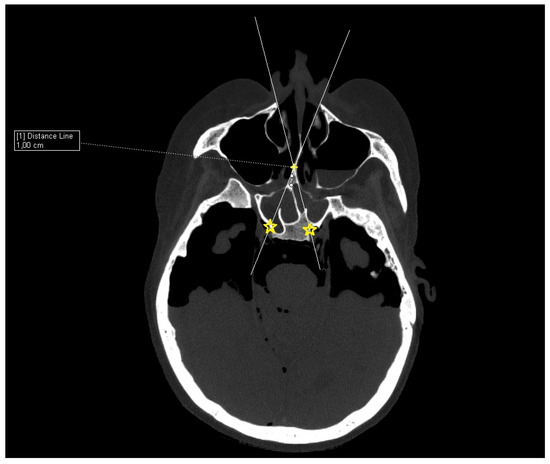

Patient CT scan: Preoperative CT scans from 20 patients with a pituitary adenoma were used for this study. The CT scans were performed on a Siemens Somatom force scanner (Siemens healthineers, Praha, Czech Republic). The measurement was performed with the SyngoVia program, using HrCT images with a slice thickness of 0.6 mm. In each patient, the semi-axial plane was created using multiplanar reconstruction by changing the angle of the axial plane to match the virtual insertion of a straight instrument during surgery through the left nasal cavity into the sphenoid cavity. The defined points for this semi-axial plane were spina nasalis anterior and dorsum sellae (Figure 1). In this semi-axial plane, at the height of the dorsum sellae, the following diameters were measured: the depth of the sphenoid cavity, the distance between the medial edges of the internal carotid arteries (ICA), the width of the pyriform aperture, and the width of the nasal cavity at the level of the attachments of the lower turbinates. The volume of the sphenoid cavity was measured with Fotom software (FOTOM 08 Plus, Ostrava, Czech Republic). Simulation of the virtual insertion of the two straight suctions (one in each nostril) was conducted in a semi-axial view at the height of the dorsum sellae. Instruments were represented with a straight white line; defined points for this white line were the lateral bony edge of the nasal aperture and the medial edge of the ICA. The intersection of the embedded virtual straight instruments (white lines) was marked with a yellow cross. The minimum septal resection required to reach the medial border of the ICA with a straightforward instrument was determined as the distance between the marked yellow cross and the anterior wall of the sphenoid cavity (Figure 2).

Figure 2. CT scan, semiaxial view, virtual straight instruments inserted into the sphenoid cavity to reach medial edge of the ICAs simulating binostril approach (white lines), crossing of virtual instruments simulating minimal septal resection needed to reach medial edge of the ICAs (yellow cross).